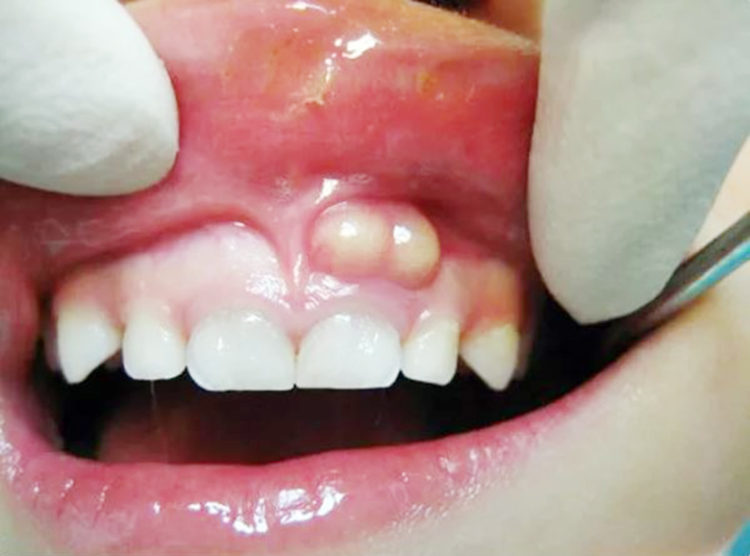

Nướu xuất hiện mụn mủ nhỏ, có thể chảy dịch.

Ban đầu, nang chân răng thường không gây đau nên nhiều người dễ chủ quan. Tuy nhiên, khi nang phát triển, bạn có thể gặp các dấu hiệu sau:

Sưng nhẹ vùng nướu hoặc mặt tại vị trí răng bị tổn thương.

Nếu không được điều trị, nang có thể phát triển lớn, phá hủy xương hàm, gây tiêu xương ổ răng, thậm chí lan sang các răng kế cận.